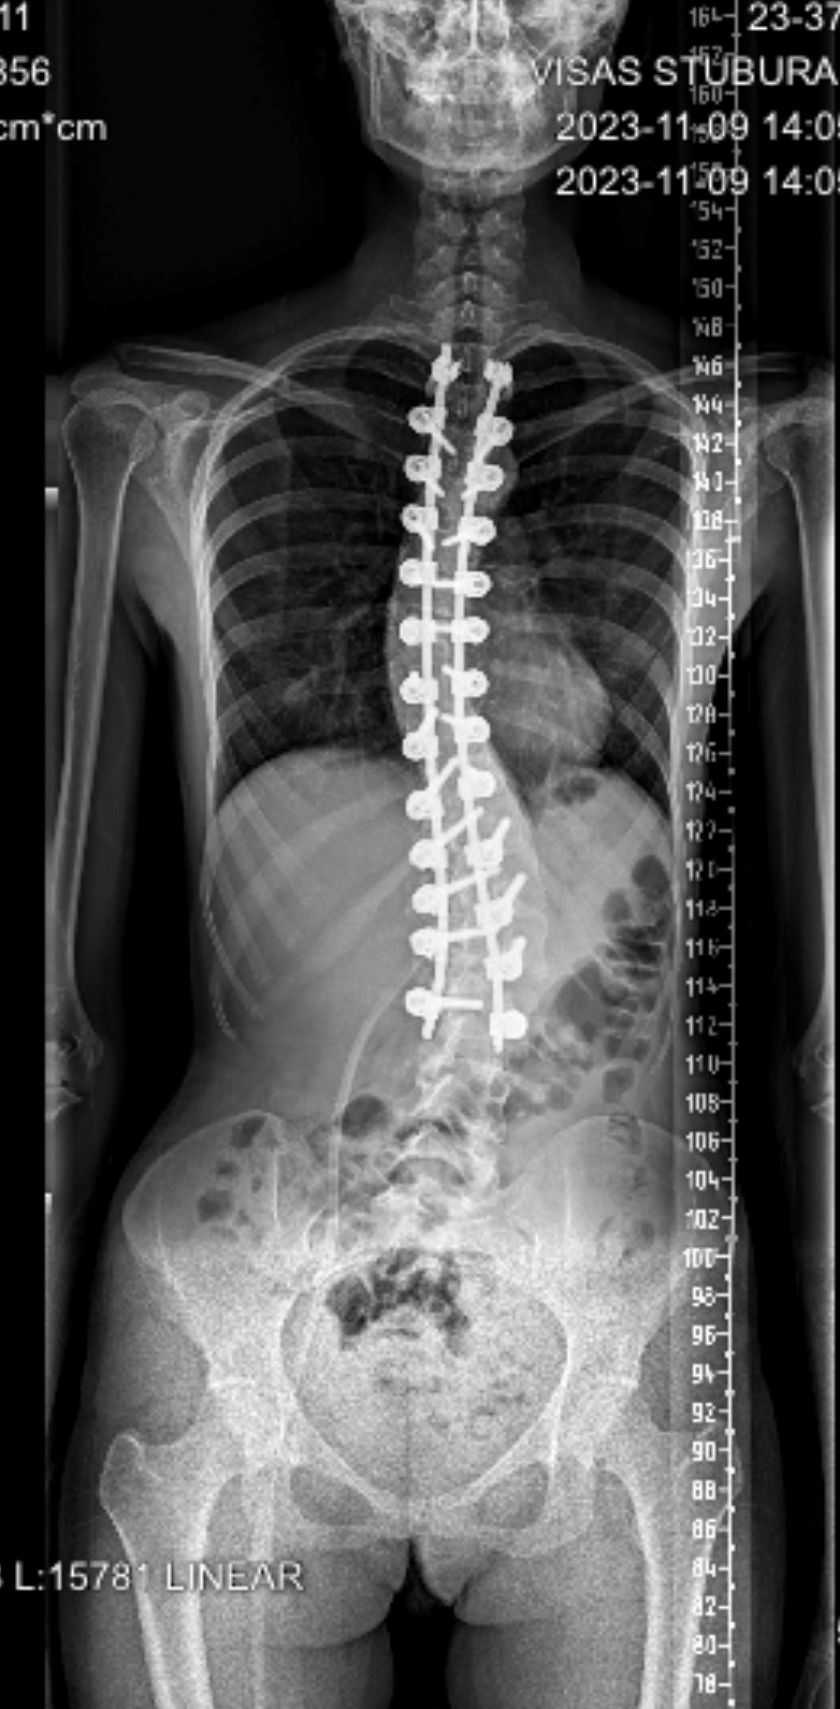

Pacientės stuburo slankstelių lūžio gydymo odisėja prasidėjo prieš trejus metus. Trauma įvyko Belgijoje, vienoje iš ligoninių atliktos dvi operacijos ir pacientė išleista į namus. „Žaizda gijo sunkiai, po mėnesio vėl patekau pas chirurgus – žaizdą dezinfekavo ir užsiuvo, – pasakoja moteris. – Jie darė prielaidą, kad tai buvo paviršinė infekcija ir išsamesnių tyrimų nusprendė atsisakyti.” Ir po šios operacijos žaizda gijo sunkiai. Moteris ir jos artimieji pasitikėjo medikais ir visa sveikatos sistema: „Per dvejus metus Belgijoje man buvo atliekami periodiniai kompiuterinės tomografijos tyrimai, deja, ten dirbantys medikai nesugebėjo pastebėti infekcijos.”

Praėjusių metų vasarą žaizdai pūliuojant pacientė kreipėsi į VUL Santaros klinikų Skubios pagalbos skyrių: „Čia ir paaiškėjo, kad su infekcija gyvenau dvejus metus, o Belgijos chirurgai šitą faktą tiesiog ignoravo. Tai buvo ir psichologiškai, ir fiziškai sunki patirtis. Anot medikų, mano sveikatos būklę galima buvo palyginti su tiksinčia bomba. Santaros klinikose man atliko visus reikiamus tyrimus, rado tą patį auksinį stafilokoką ir skubiai paguldė į ligoninę. Gydytoja Ona Lapteva pranešė, kad stuburo implantai infekuoti ir likęs tik vienas pasirinkimas – juos pakeisti naujais, – pasakoja pacientė. – Belgijos gydytojams pranešiau apie savo situaciją. Jie pasakė jokiu būdu neliesti nugaros smegenų, nes didelė tikimybė, kad operacija nepavyks ir aš galiu nevaikščioti…” Po 9 savaičių gydymo moteris džiaugiasi rezultatu: „Nors daug skausmingo, sunkaus teko patirti, išgyventi, visgi galiu pasidžiaugti, kad susipažinau su nuostabiais žmonėmis – gydytojais bei visu personalu – ir supratau, kaip gera savo šaly turėti tokių profesionalių ir dėmesingų specialistų.”